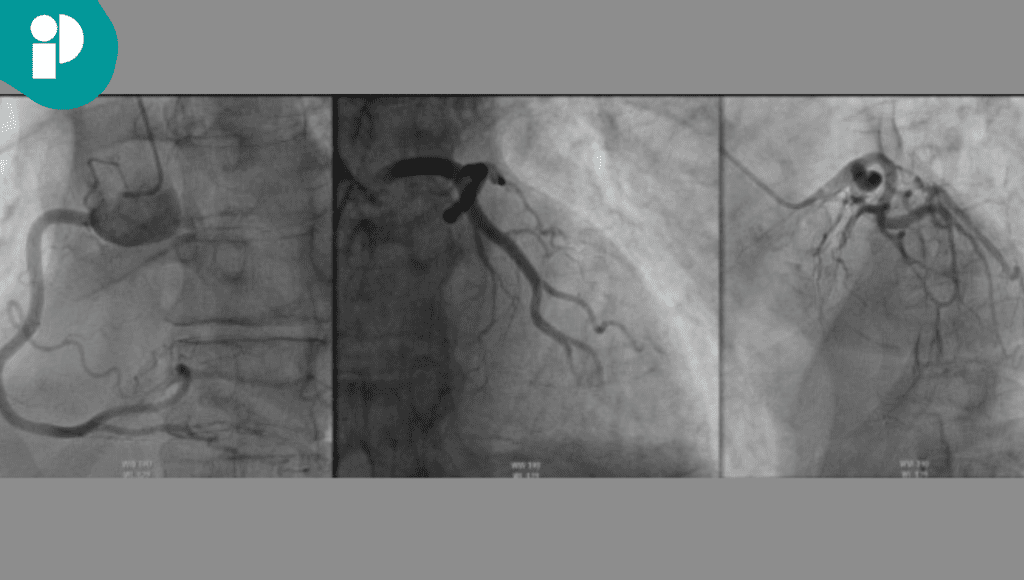

Ante la sospecha inicial de miocarditis inducida por ICI (una complicación grave que suele obligar a suspender la inmunoterapia por el alto riesgo de desenlaces adversos) el equipo clínico optó por realizar estudios cardíacos avanzados. La resonancia magnética cardíaca y la biopsia endomiocárdica fueron determinantes para descartar la miocarditis y confirmar el diagnóstico de síndrome de Takotsubo.